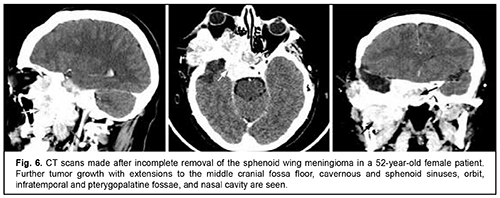

Craniofacial meningioma usually develops due to incompletely removed olfactory fossa meningioma, sphenoid wing meningioma or middle cranial fossa meningioma. A meningioma in any of the above locations, if incompletely removed (particularly, incompletely removed skull base infiltration) may become the origin of the subsequent growth on the inner and outer skull surfaces. We noted intra- and extra-cranial growth of primary meningioma at the ethmoid labyrinth, medial middle cranial fossa and medial posterior cranial fossa. Fig. 6 exemplifies the further spread of the sphenoid wing meningioma to the middle cranial fossa floor, cavernous and sphenoid sinuses, orbit, infratemporal and pterygopalatine fossae, and nasal cavity after incomplete tumor removal. It is noteworthy that, within the field of ophthalmic oncology, sphenoid wing meningiomas constitute a major portion of the large tumors of the anterior skull base and orbit. The tumor extends intracranially and extracranially from the pterygopalatine fossa, leading to destruction of the floor of the medial middle cranial fossa and the involvement of the cavernous sinus (Figs. 7, 8).